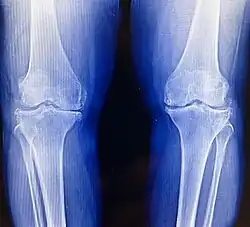

Imaging tests like X-rays are commonly utilized to diagnose and monitor arthritis.[61] Other imaging tests for rheumatoid arthritis that may be considered include computed tomography (CT) scanning, positron emission tomography (PET) scanning, bone scanning, and dual-energy X-ray absorptiometry (DEXA).[61]

Osteoarthritis (OA) is the most common form of arthritis.[62] It affects humans and other animals like dogs, cats, and horses. It can affect both the larger joints (i.e. knee, hip, shoulder, etc.) and the smaller joints (i.e. fingers, toes, foot, etc.) of the body. Caused by daily wear and tear of the joint, this can speed up its progression. OA results from cartilage breakdown, leading to bones rubbing directly and eroding each other. The symptoms typically begin with minor pain during physical activity, but can eventually progress to be present at rest. The pain can be debilitating and prevent one from doing activities that they would normally do as part of their daily routine. OA typically affects the weight-bearing joints, such as the back, knee and hip due to the mechanical nature of this disease process. Unlike rheumatoid arthritis, OA is more common in the elderly, with increased age being the strongest predictor, likely due to declining chondrocytes ability to maintain cartilage.[63] Over 30 percent of women have some degree of OA by age 65. Diagnosis consists of the primary tools for diagnosing OA are X-rays of the joint. Findings on X-ray that are consistent with OA include those with joint space narrowing (due to cartilage breakdown), bone spurs, sclerosis, and bone cysts.[64]